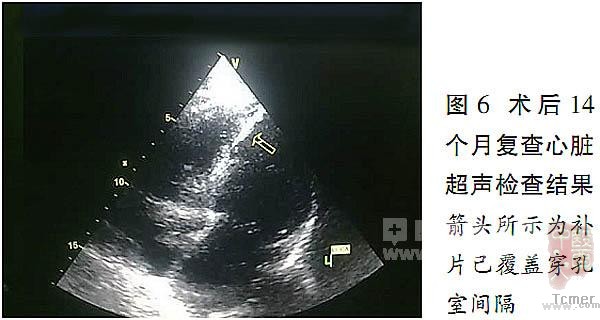

患者于术后14个月接受了随访检查。

患者临床情况稳定,心脏超声检查结果(图5、6)显示,室间隔补片上端见极微量左向右分流,EF为42%。